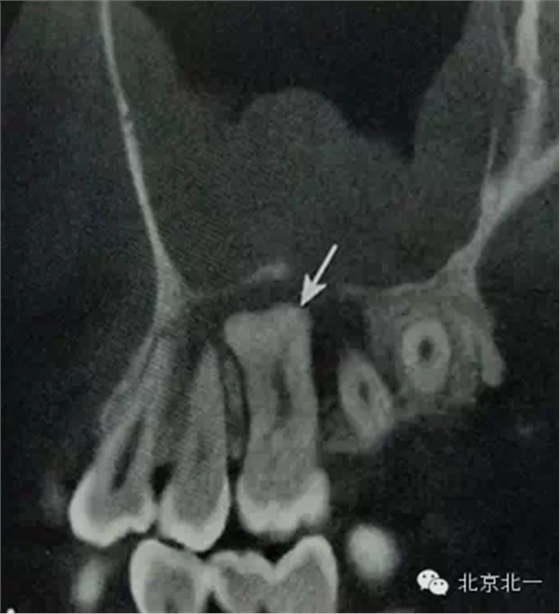

【CBCT表現(xiàn)】:

牙骨質(zhì)增生可表現(xiàn)為整個(gè)牙根體積的膨大,或僅表現(xiàn)為根尖呈球狀增生,對(duì)于多根牙,體積的膨大可局限于個(gè)別牙根,不伴根尖周感染的情況下,便便牙牙周膜及硬骨板影像相連續(xù)、完整。部分病例可見(jiàn)牙周膜間隙消失,牙根與牙槽骨粘連,導(dǎo)致牙齒萌出障礙或者滯留。

B6腭根根尖區(qū)膨大,牙周膜和骨硬板消失,根尖周見(jiàn)低密度影,上頜竇下壁骨質(zhì)不連續(xù),B B6頜面已開(kāi)髓。